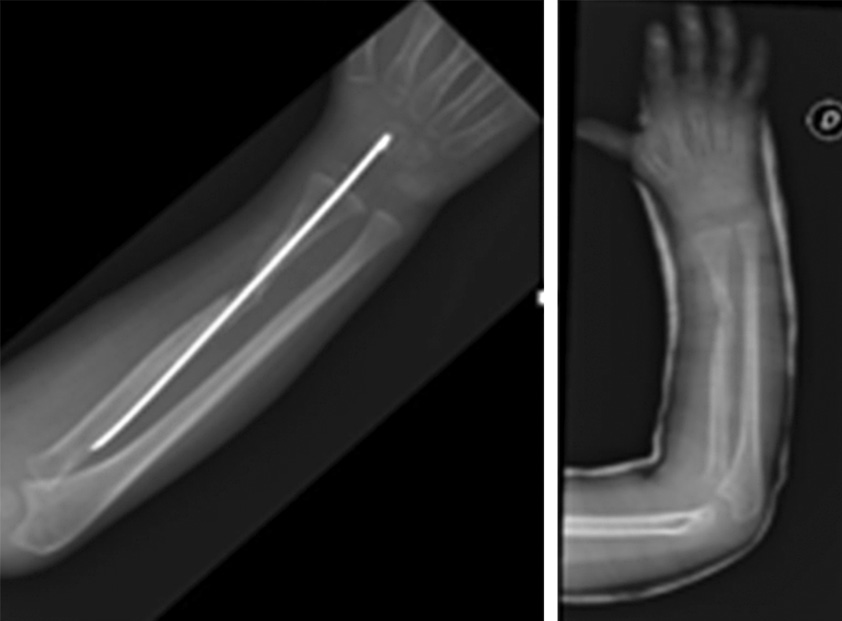

Клинически, как и по данным рентгенологического исследования, у пациента наблюдалось местное улучшение. Спустя 6 мес. после последней трансплантации спица Киршнера была удалена. При контрольном осмотре через 28 мес. у пациента зарегистрированы полная консолидация начального участка несращения, отсутствие нейроваскулярной недостаточности и суставной недостаточности. Больного можно считать выздоровевшим (рис. 7, 8).

Рис. 7. Рентгенограмма после удаления спицы Киршнера через 28 мес. после травмы